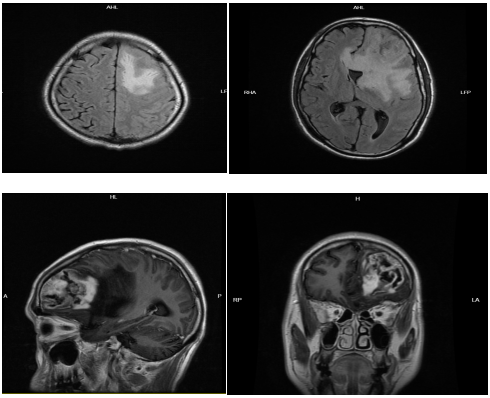

今年57歲的羅叔是貴州省黔西南州冊亨縣當(dāng)?shù)匾幻家雷宕迕?,一個(gè)多月前突然出現(xiàn)頭暈、頭痛,并伴有反應(yīng)遲鈍、言語笨拙、找詞困難的癥狀。到冊亨縣人民醫(yī)院就診檢查后被診斷為顱內(nèi)腫瘤,考慮為腦膠質(zhì)瘤,危險(xiǎn)性大,迫切需要手術(shù)治療。家屬聽后焦急萬分!

“腫瘤位于左側(cè)大腦半球,屬于功能區(qū),容易引起語言和肢體運(yùn)動(dòng)的障礙。手術(shù)盡可能地要把它完整切除,同時(shí)要保護(hù)正常的功能不受影響。”李雪松博士指出。

患者在全麻下行左側(cè)腦內(nèi)占位病變切除術(shù)。術(shù)中,主刀醫(yī)李雪松博士、助手文世宏主任在顯微鏡下仔細(xì)操作,逐漸暴露出腫瘤。手術(shù)過程也是教學(xué)過程,惠州三院專家團(tuán)隊(duì)充分發(fā)揮“傳幫帶”精神,從手術(shù)體位的擺放、切口入路、手術(shù)技巧等方面,為冊亨縣人民醫(yī)院同行提供技術(shù)解說。看到李雪松博士精湛的手術(shù)技巧,聆聽專家的精彩講解,讓手術(shù)現(xiàn)場的醫(yī)護(hù)人員受益匪淺。